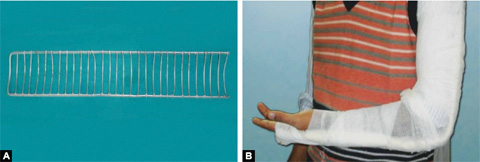

Cramer Wire Splint (Figs. 1.29A and B)

It is made up of two thick and parallel wires with many interlacing wires (ladder splint). It is a flexible splint which can be bent in different shapes to accommodate different body parts. It is used for temporary splintage of fractures of both upper and lower limbs during transportation.